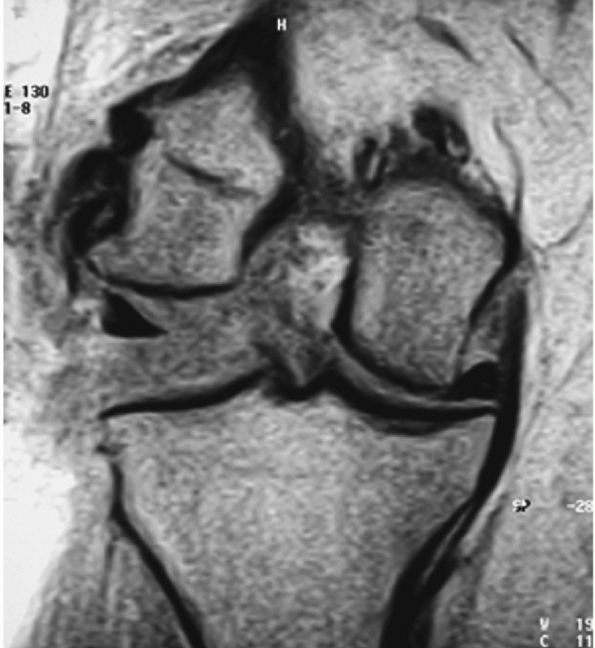

![]() |

FIGURE 54-4

Magnetic resonance images of a dislocated knee with complete tears of the medial collateral ligament (MCL), posterior cruciate ligament (PCL), and anterior cruciate ligament with a “peel-off” lesion of the PCL (A) and a tibial avulsion of the MCL on the coronal T1-weighted magnetic resonance image (B). |